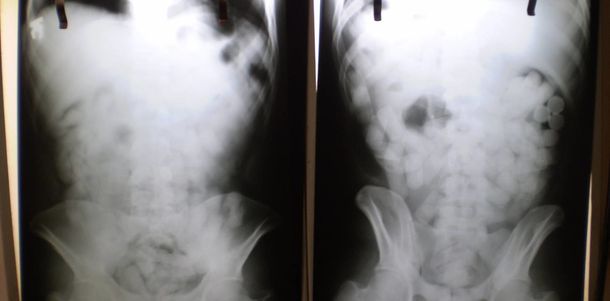

Tras un control con escáner corporal, se confirmó que transportaba múltiples cuerpos extraños en su interior. Fue inmediatamente internado en el Hospital de Ezeiza, donde permaneció bajo estricta vigilancia médica y policial durante cuatro días, período en el cual evacuó las 90 cápsulas que totalizaron 698 gramos de cocaína.